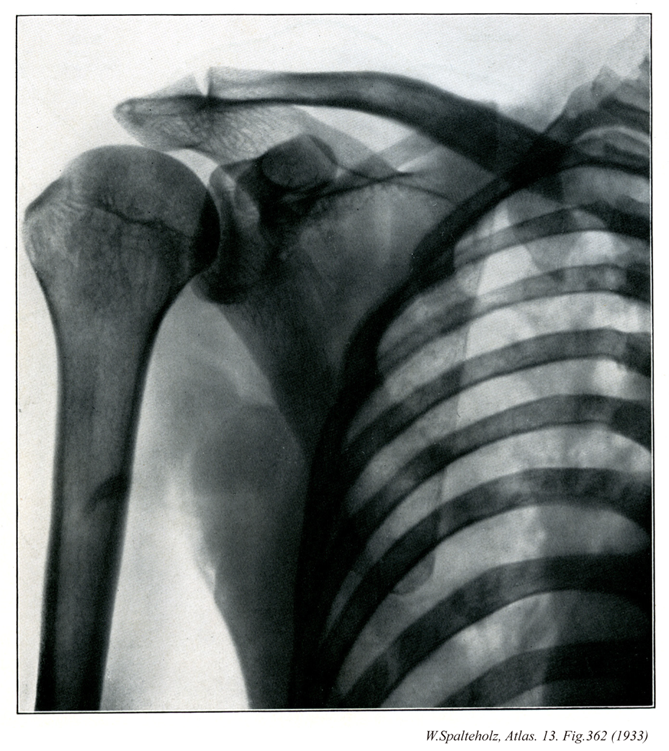

362

- 362_00【Pectoral girdle; Shoulder girdle上肢帯;胸帯;肩帯 Cingulum pectorale; Cingulum membri superioris】 Its skeletal framework consists of the scapulae and the clavicles.

→(上肢帯とは肩(肩甲部)に相当し、体幹と上腕とを結合する役目をする(骨では鎖骨と肩甲骨が上肢帯骨である)。上腕と体幹との移行部で肩関節を包んでいる範囲を肩というが、その広がりははっきり規定されていない。)